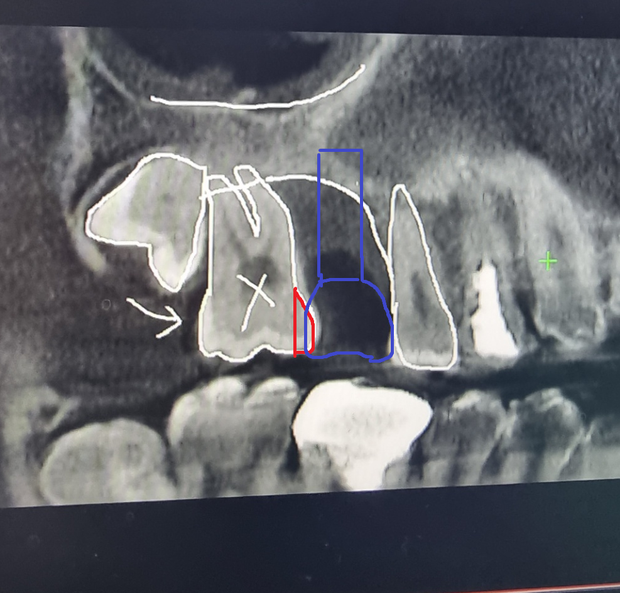

원래 치료 순서로는 아래 사진과 같이

6번 어금니 발치- 7번 어금니 옆을 좀 깎은후 6번에 임플란트 진행하는쪽으로 하였으나

(파란색,빨간색 부분만 봐주시면 되겠습니다)

• 1번 째 사진